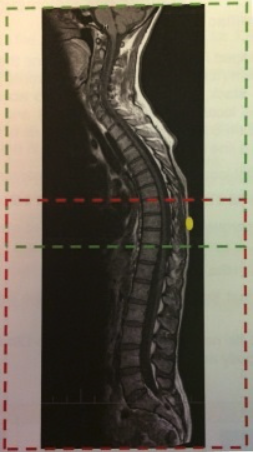

- This is a study of the spine and SI joints for Ankylosing Spondylitis. A marker needs to be placed on the patients’ back at the same level as the xiphoid process. The spine is done in two jumps. The two stacks for the total spine need to overlap covering the marker and cover from C1 through S2 (see Fig. 1). If unable to do in two jumps, can do in 3 jumps – change FOV to 300x300 (do not change any other parameters)

Fig. 1- SAG Stack Planning and Marker Placement